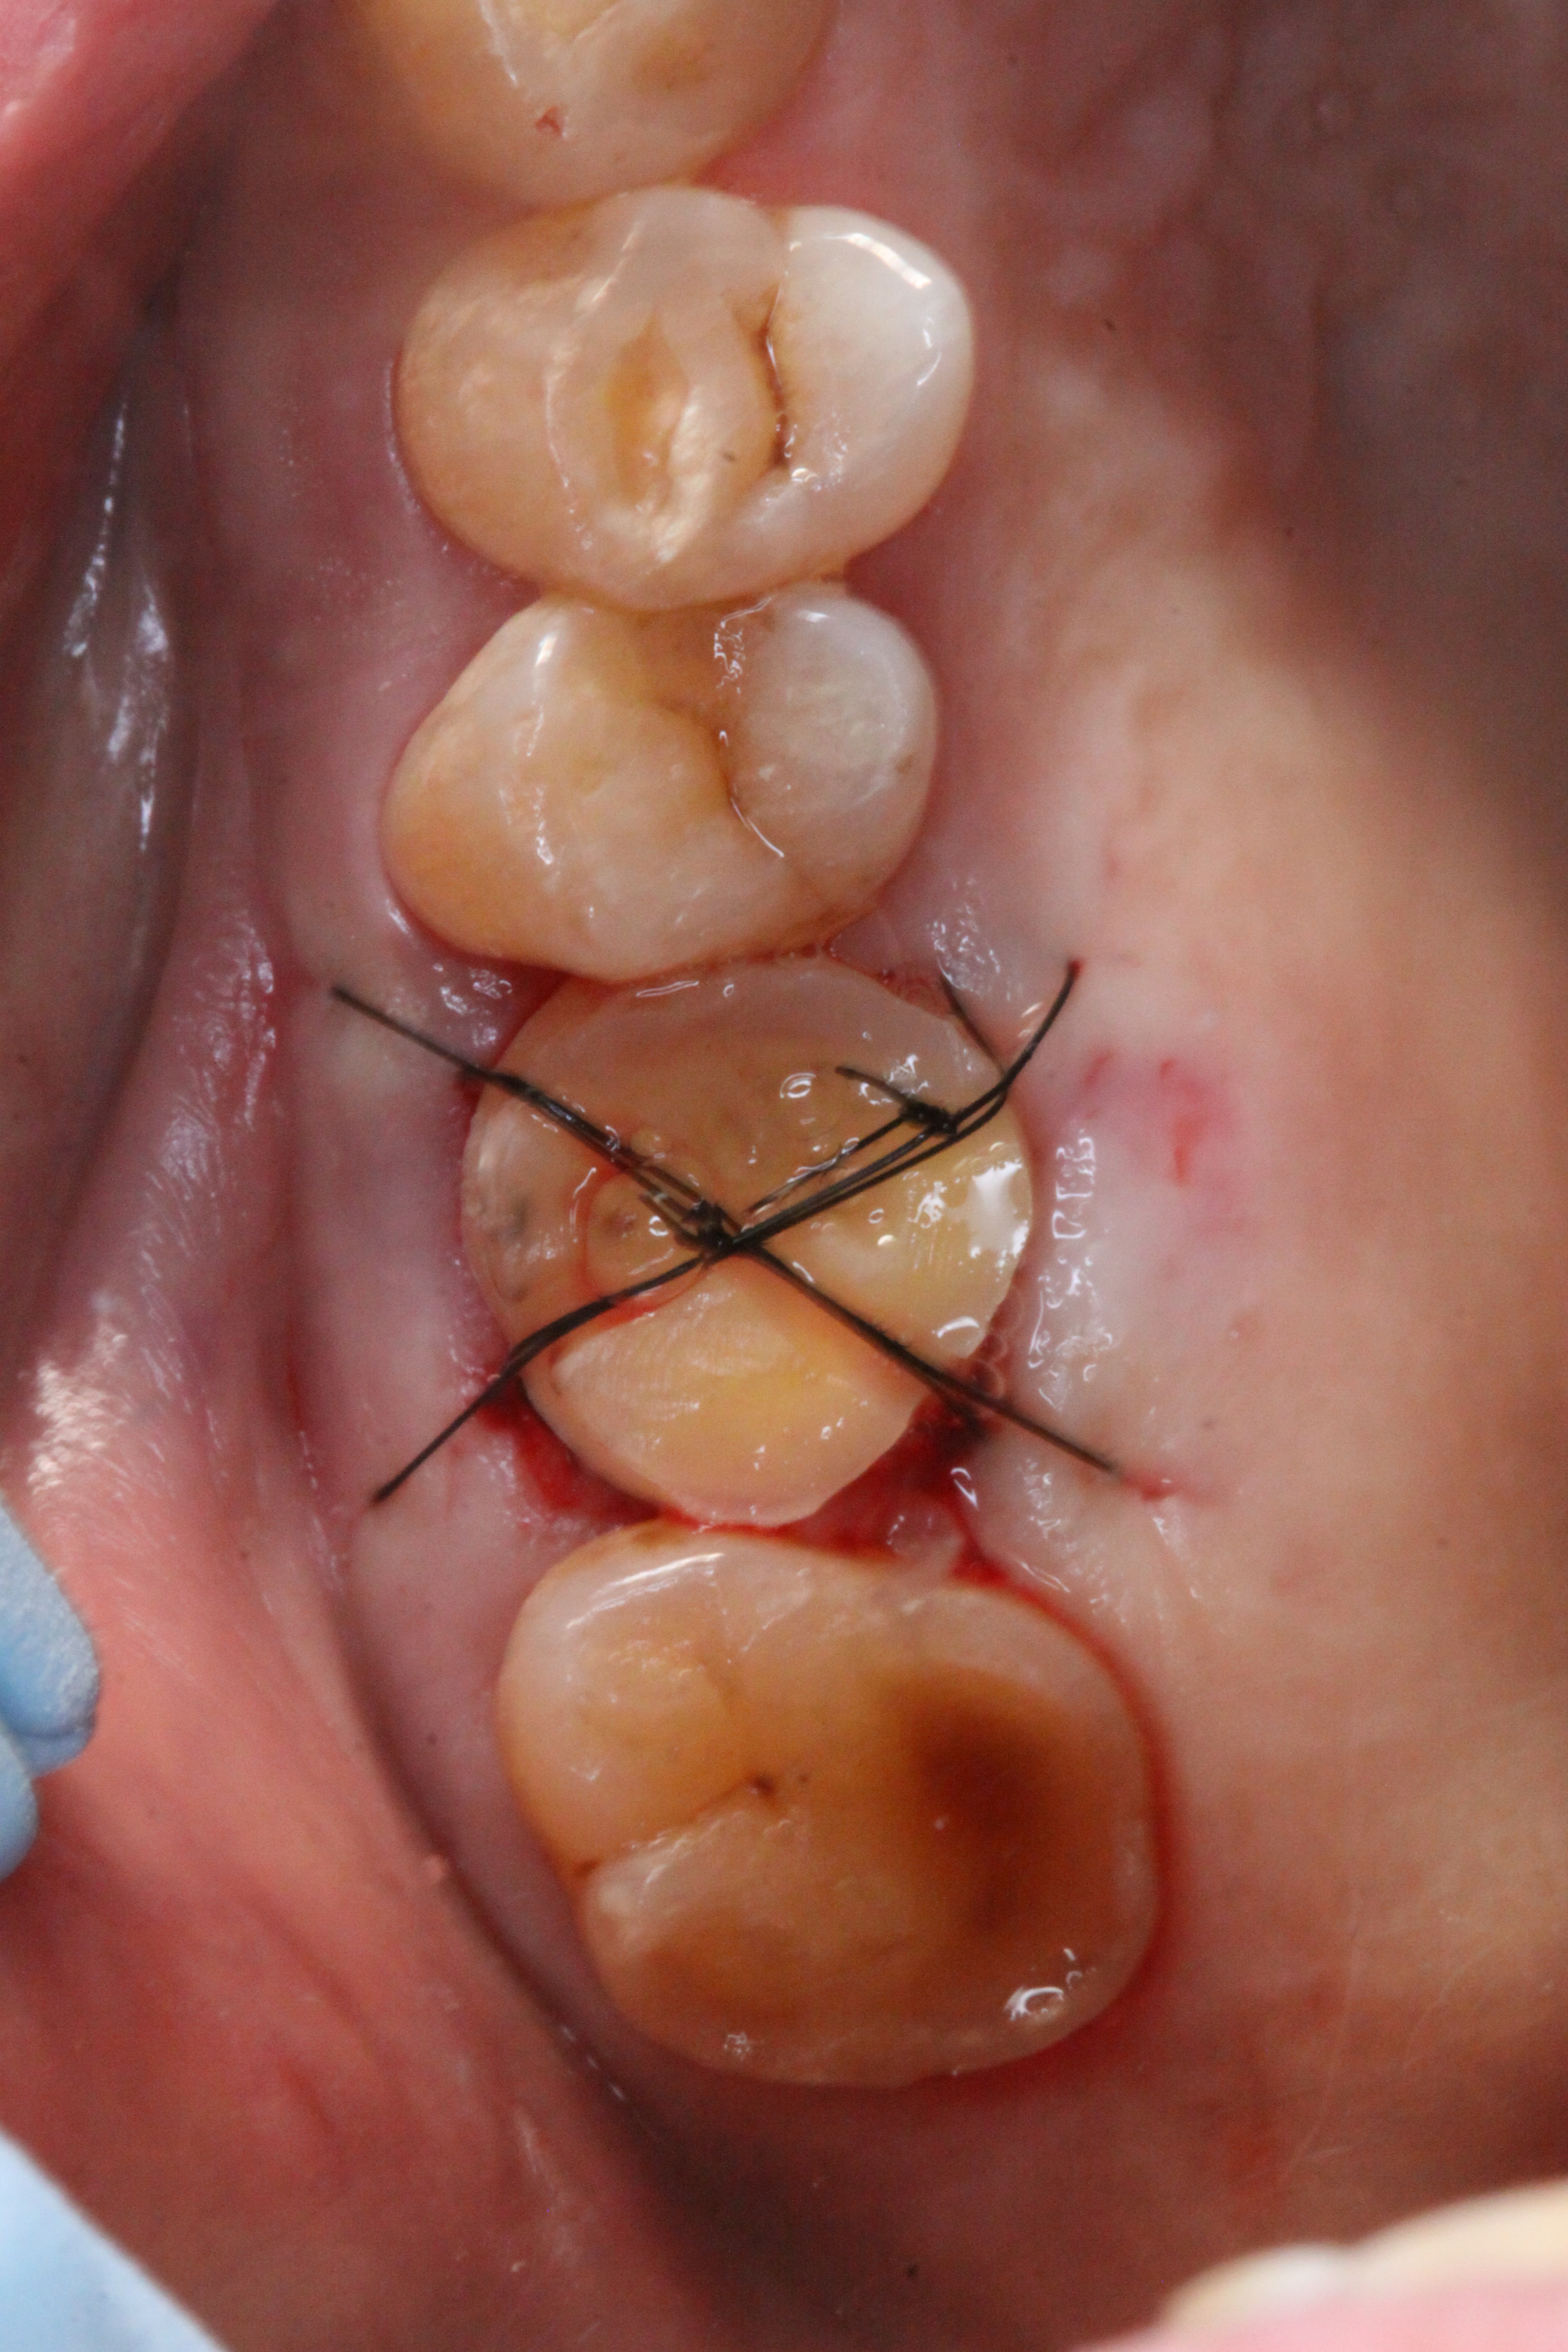

移植に関しては歯茎を開いたり、骨を削って調整して歯を入れるので数日の間、腫れや痛み、出血を伴う可能性があります。

移植後

左下の親知らずを移植。

数週間開けて根管治療を行います。